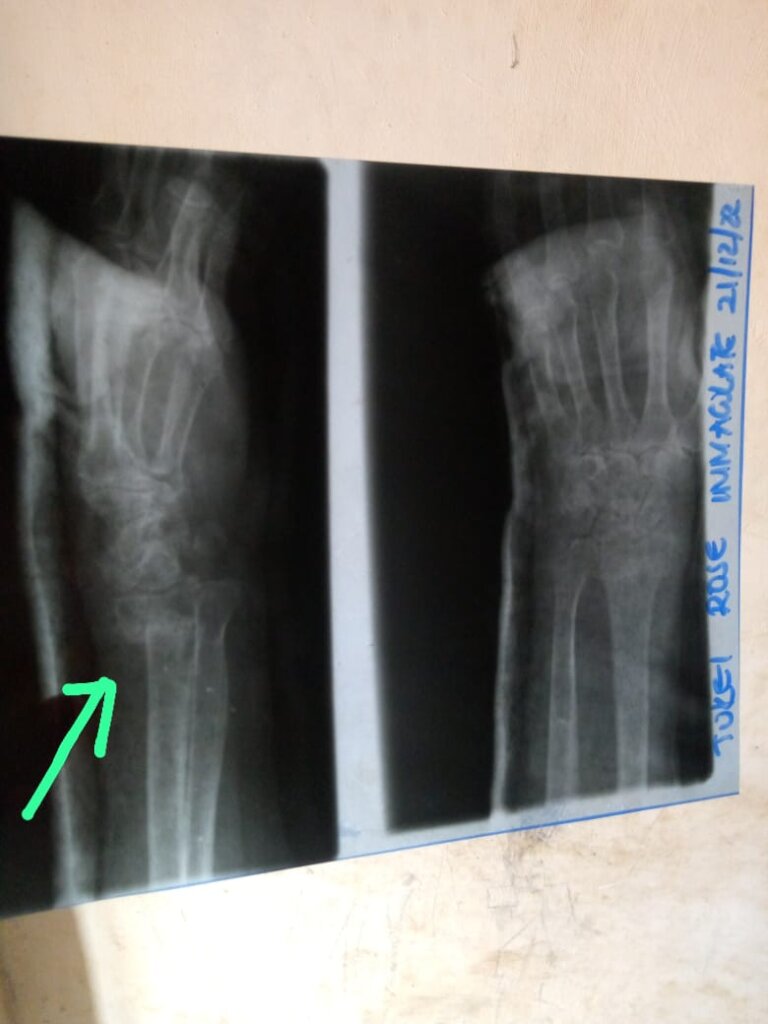

Our rural health clinic has no Orthopedic surgeons, doctors who specialize in the musculoskeletal system - the bones, joints, ligaments, tendons, and muscles that are so essential to movement and everyday life. With more than 200 bones in the human body, it's an in-demand specialty.

![X-ray results]()

X-ray results